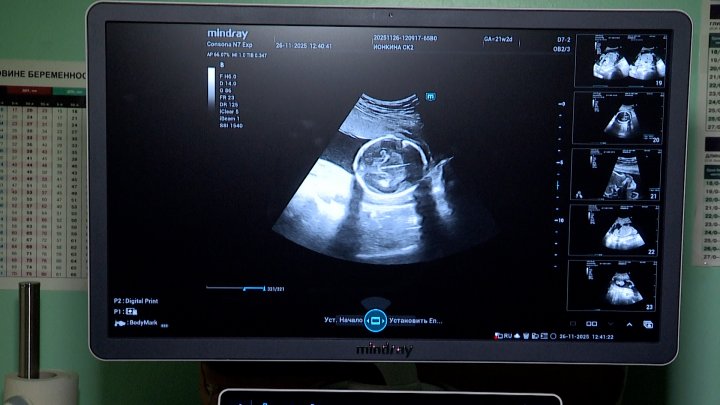

Долгожданный звук сердцебиения маленького чуда ждет с трепетом и нетерпением будущая мама. Такие плановые обследование проходя каждые три месяца беременности. Первый скрининг на 12–13 неделе для проверки правильного развития и исключения рисков. Второй — на 19–21 неделе, когда специалисты оценивают работу органов и исключают пороки. Третий скрининг на 30–34 неделе оценивает рост, положение, работу плаценты и количество вод, готовя маму к родам.

Благодаря новому аппарату УЗИ все записи на экране сохраняются в файлы, что упрощает работу врача. Но самым приятным на приеме становится ультразвуковая живопись, так ее называют специалисты, теперь будущая мама может увидеть своего малыша до рождения и понять, на кого он похож больше. В отделении ультразвуковой диагностики в акушерстве и гинекологии трудятся всего два специалиста — Мария Сальникова и Виктория Колесова. Ежегодно они проводят более двух тысяч исследований для будущих мам, помогая наблюдать, как развивается новая жизнь.

Мария САЛЬНИКОВА, врач ультразвуковой диагностики КБ№42 ФМБА России: «С аппаратом Mindray Consona N7 экспертного класса, конечно, более точное исследование проводится, более четкая картинка стала и проводит все расчеты, которые нужны нам именно в акушерстве. Потихоньку мы его осваиваем, пока очень нам тяжело, но все идет, с каждым днем все лучше и лучше, я думаю, что прогресс будет».